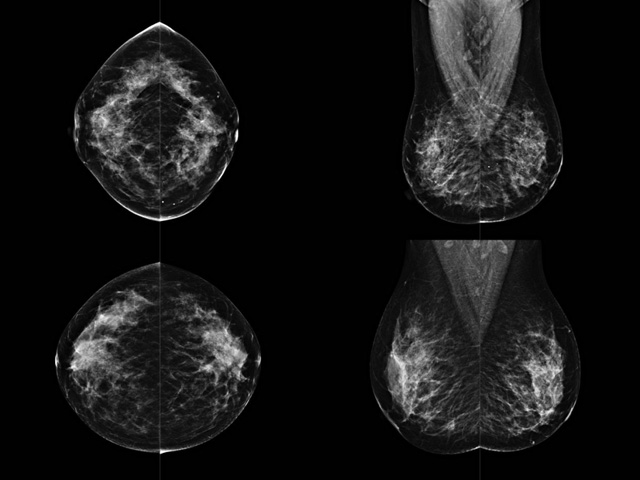

乳腺DR檢查的作用跟有什么細(xì)節(jié)需要注意事項

乳房檢查時候要注意一些細(xì)節(jié),需要更深入的了解這樣才能使檢查更準(zhǔn)確。乳腺DR是乳腺癌的篩查診斷工具設(shè)備。是乳房方面檢查的重要影像方法。它可以臨床檢查出早期的乳腺癌??梢耘袛嗔夹詯盒浴R驗樗梢詸z查出早期的病變。對良性惡性檢查的準(zhǔn)確率達(dá)到90%以上。發(fā)病高峰年齡為45歲到54歲。50歲檢查出來乳腺癌病患,可以讓死亡率下降3成。所以30-40歲女性每年做一次乳腺DR檢查。40歲以上就一年兩次。如果家族史有乳腺癌的30歲以下也需要做檢查。清晰顯示乳腺各層組織嚴(yán)重的乳腺增生,乳腺炎,乳腺外傷也建議1年檢查一次。極大提高了早期乳腺癌的敏感度和診斷率。

大角度、高質(zhì)量的乳腺檢查,可以讓女性帶來身體健康安全。為醫(yī)生提供了高清影像數(shù)據(jù)。乳腺檢查時候各個部位影像顯示出來。白色乳腺導(dǎo)管跟纖維結(jié)締組織。模糊的是脂肪。病變一般是不透明的白色。有需要放大來檢查。乳腺DR沒有重疊偽影。輻射劑量更少。因為乳腺癌發(fā)病每年都有所提高,對女性都造成了嚴(yán)重的身體健康危害。早做檢查早治療是不可忽視的舉措??梢源蟠蟮慕档?/span>死亡率。保證身體健康。一般檢查避開經(jīng)期,來完7天左右是最佳的檢查時間。絕經(jīng)的女性就沒有要求。孕婦不參加乳腺DR檢查, 6個月內(nèi)準(zhǔn)備妊娠的婦女也不宜行此檢查。